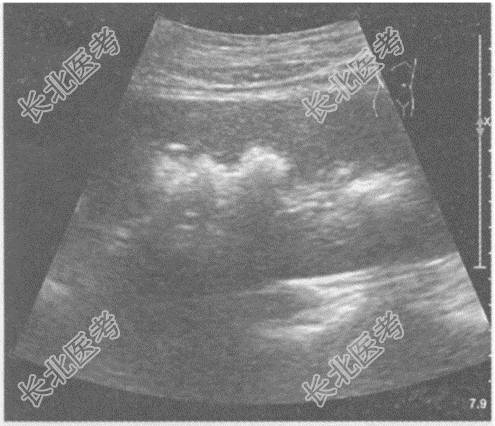

- 单项选择题临床资料:女, 25岁,因反复四肢麻痹10年, 腰部疼痛、肉眼血尿3月余入院。

化验检查:尿常规红细胞3+。

超声综合描述: 双肾形态、大小正常,沿肾锥体分布可见多个强回声光团, 后伴声影。

超声提示: A、双肾钙乳症

B、双肾海绵肾

C、双肾多发结石

D、双肾多发钙化

E、双肾错构瘤